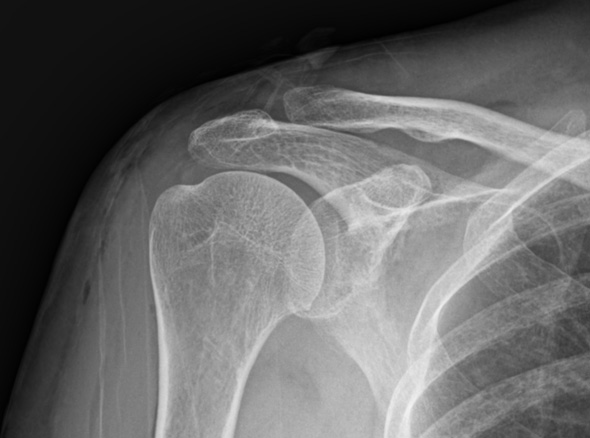

수차례 충격파 치료 등에도 호전되지 않는 경우

주사 흡인술이 가능하지 않은 경우(오래되거나 딱딱한 석회)

1-2Cm 이상의 큰 석회

운동 범위의 감소가 매우 큰 경우

힘줄 파열이 동반되어 있는 경우